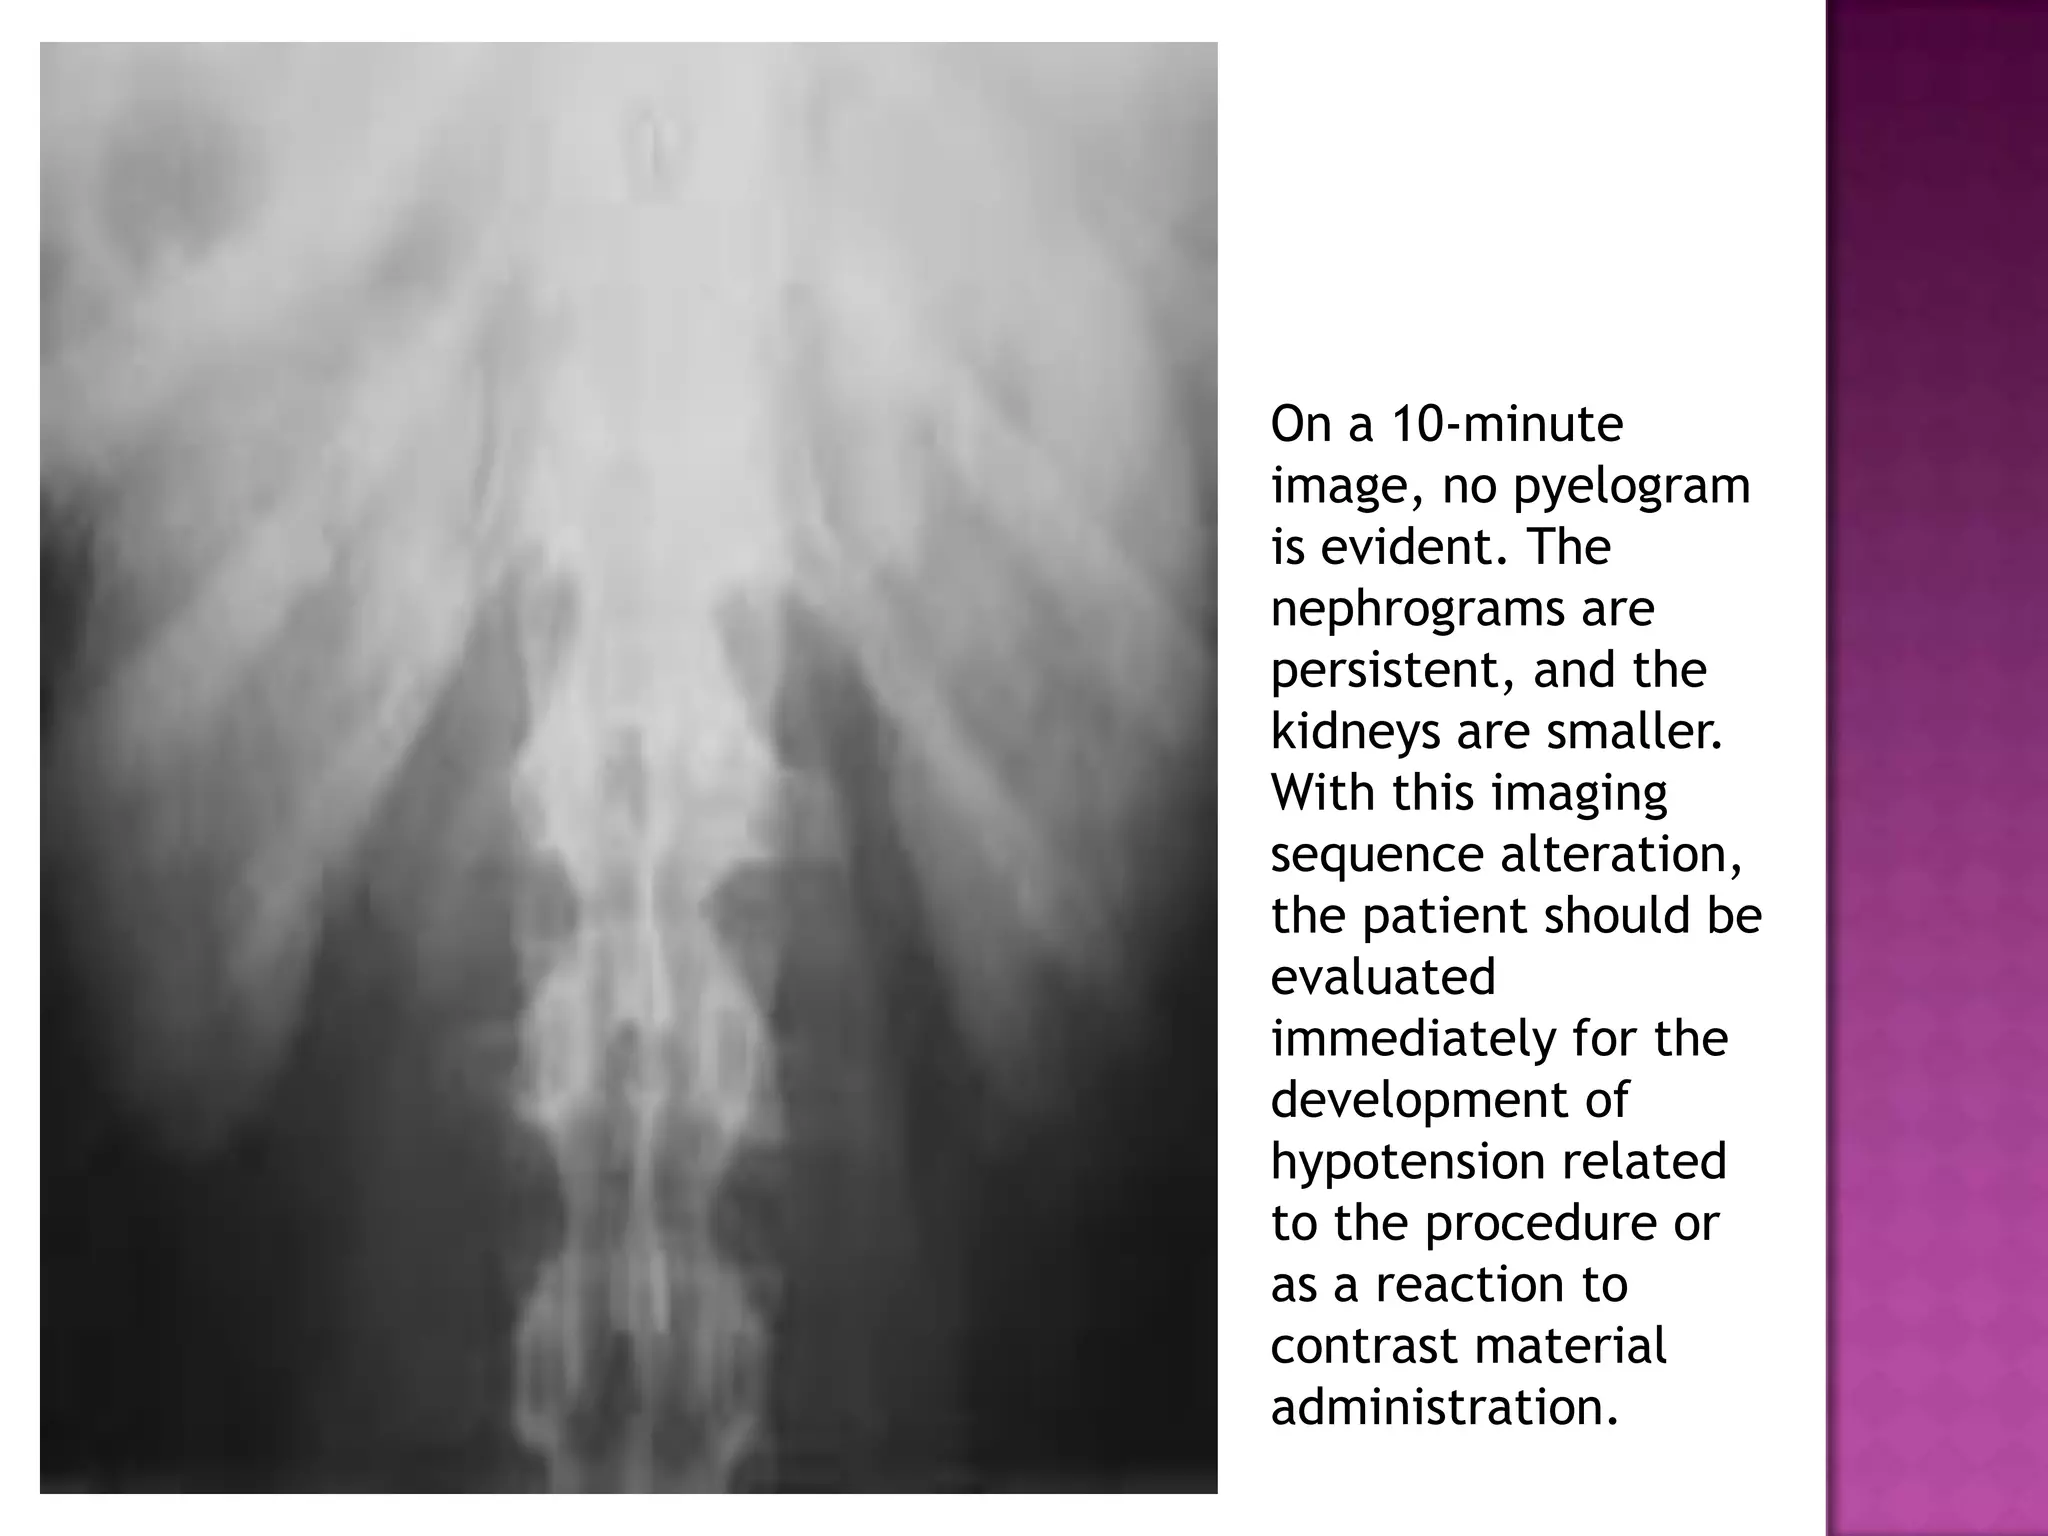

On a 10-minute

image, no pyelogram

is evident. The

nephrograms are

persistent, and the

kidneys are smaller.

With this imaging

sequence alteration,

the patient should be

evaluated

immediately for the

development of

hypotension related

to the procedure or

as a reaction to

contrast material

administration.

On a 10-minute image,no pyelogram is evident. The nephrograms are persistent, and the kidneys are smaller. With this imaging sequence alteration, the patient should be evaluated immediately for the development of hypotension related to the procedure or as a reaction to contrast material administration.